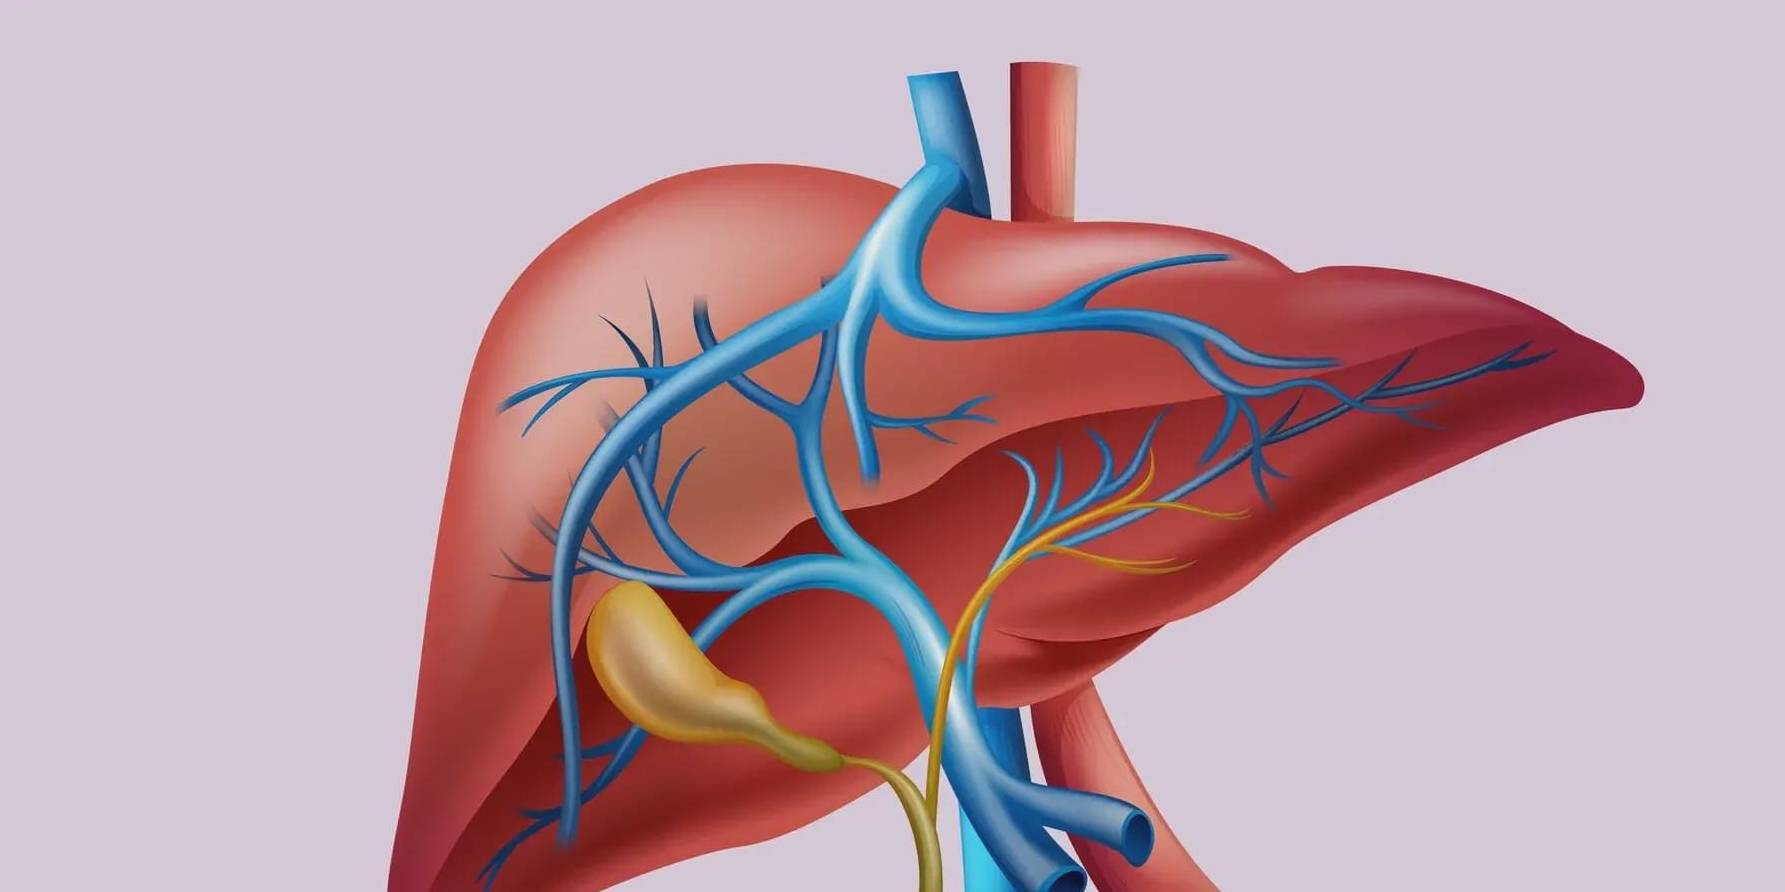

肝脏或者胆道系统的疾病 , 引发的疼痛通常位于右上腹 , 比如肝癌、一些大的血管瘤和肝囊肿、胆结石、胆囊炎等 。 有时候这些疾病导致的疼痛 , 会放射到后背、右肩膀以及上腹部的正中等部位 。

文章图片